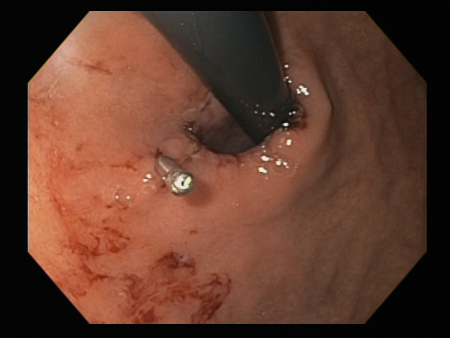

Um clipe do tipo "through-the-scope" instalado no centro da lesão (sem infusão prévia de adrenalina, neste caso)

Do acervo de Juan Carlos Munoz, MD, University of Florida